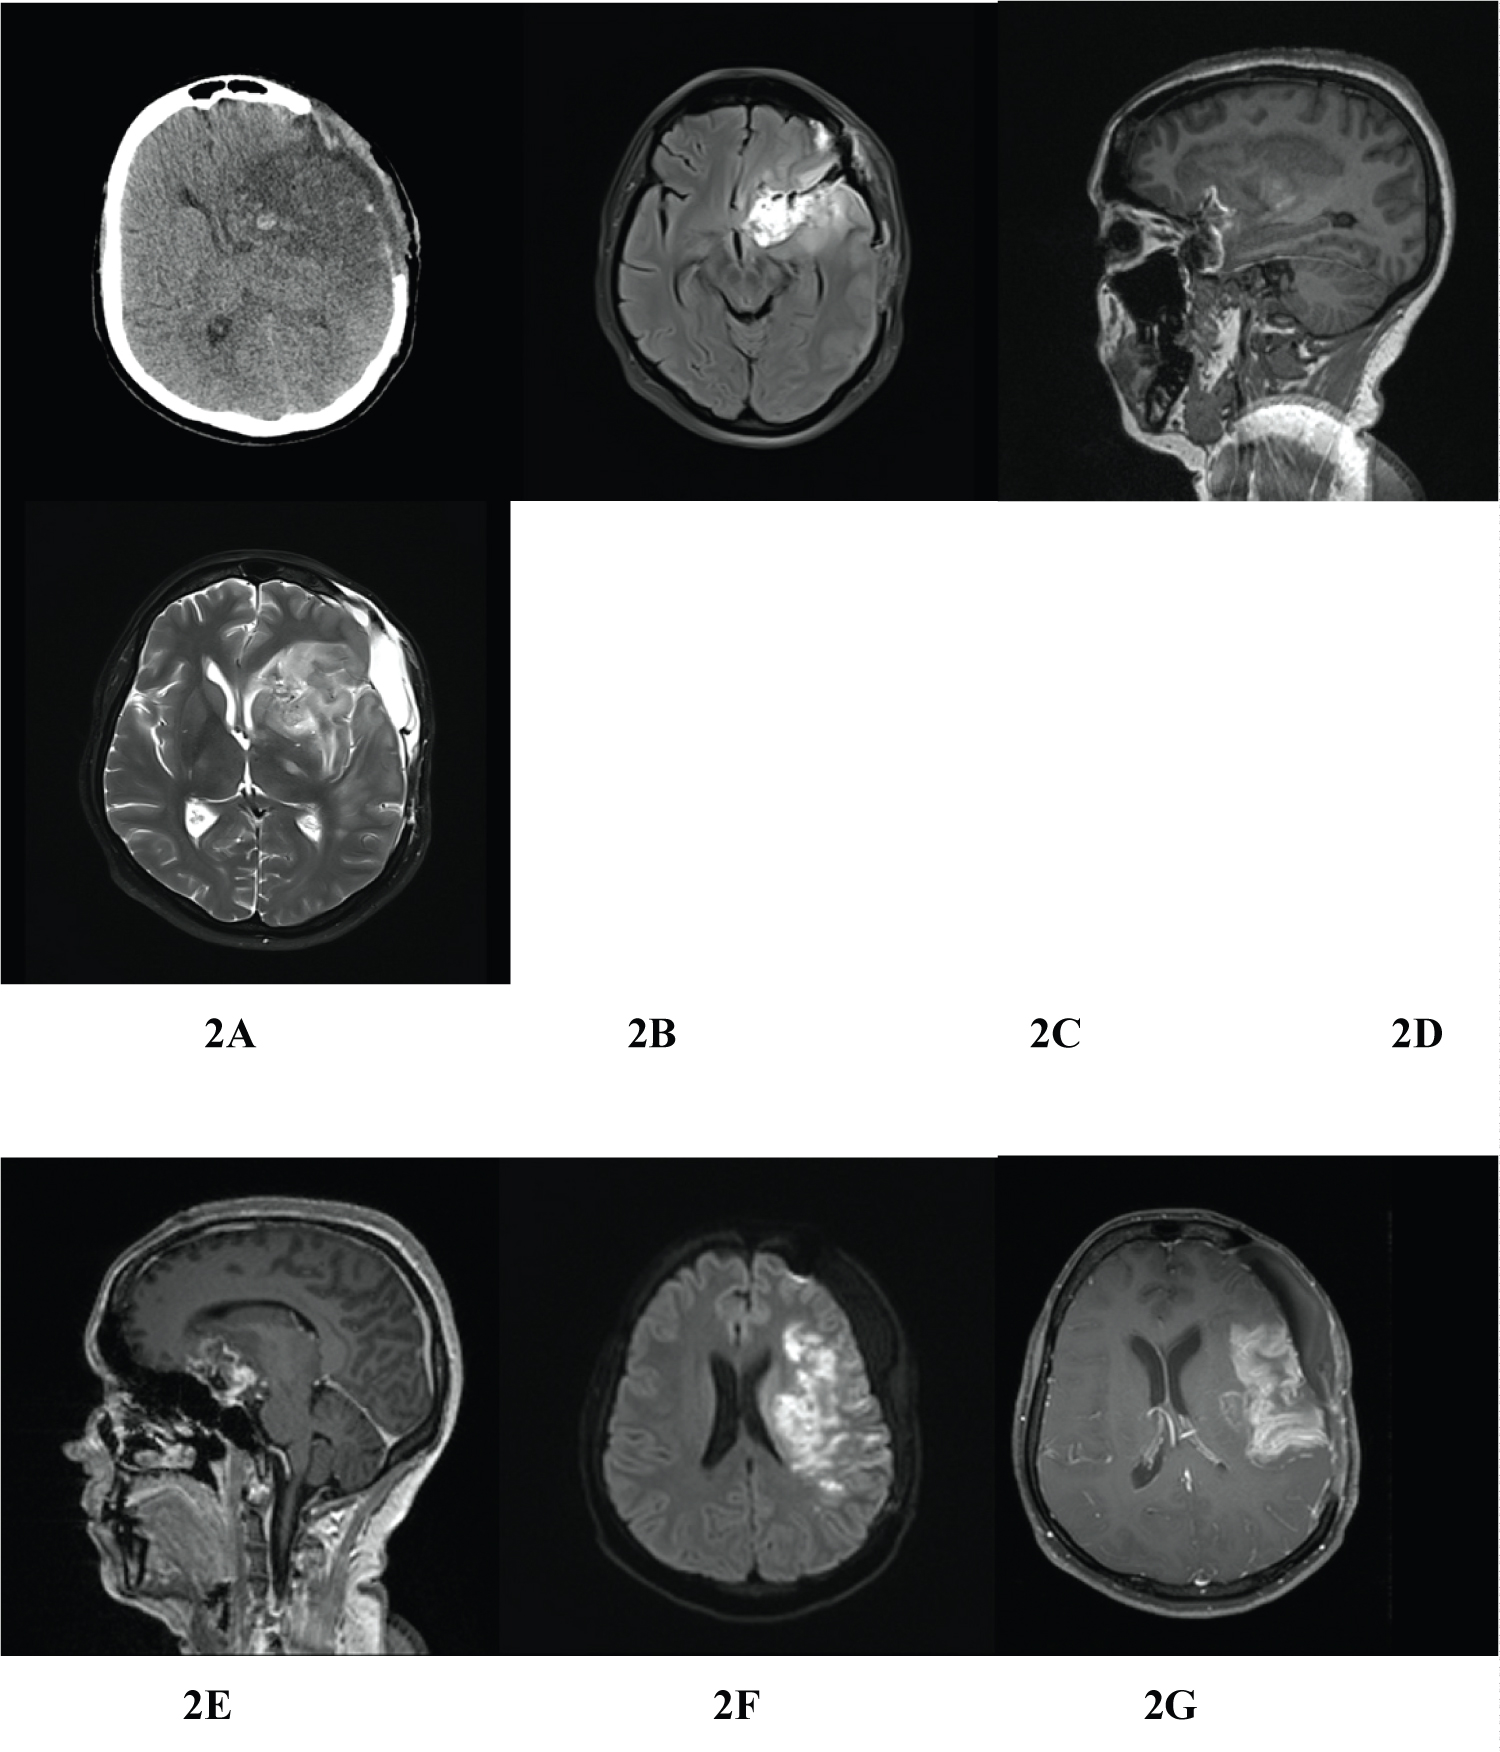

Figure 2: Postoperative images; plain CT scan of brain shows left MCA infarct and no evidence of residual tumor (A), contrast MRI of brain showing edema in and around the operated area with left MCA infarct and no evidence of residual tumor (B-G). View Figure 2

She underwent emergency left pterional craniotomy, large bone flap was raised, and lateral sphenoid ridge was shaved for better visualization of operating area. Gross total excision (Simpson grade III) of meningioma was achieved. Intraoperative findings were solid, hard and vascular extra axial mass attached to left clinoidal and planum sphenoidal areas and had encased ICA and M1 segment; there was complete occlusion at left M1 segment by thrombus and was confirmed by TCD (transcranial doppler) and ICG (indocyanine green) angiography. There was tremendous amount of brain edema during procedure so bone flap was removed and laxed duroplasty was done. Post-operatively patient was kept on ventilator for 72 hours and then extubated. The size of the left pupil regressed just after surgery. On 3 rd post op day, patient was fully conscious but she remained right sided hemiplegic and aphasic. Postoperative images (CT/MRI) showed no residual tumor except areas of brain edema and infract (Figure 2A, Figure 2B, Figure 2C, Figure 2D, Figure 2E, Figure 2F and Figure 2G). After three weeks of vigorous physio and speech therapy she was able to walk with support and spoken few words. Histopathology report was described as increased areas of cellularity, foci of necrosis, composed of meningoepithelial cells arranged in whorls pattern with occasional mitotic figures which are suggestive atypical meningioma (WHO Grade II) (Figure 3A, Figure 3B and Figure 3C). Since patients had Simpson grade III excision (gross total excision) we decided to have close observation with regular follow up and did not recommend for either radio or chemotherapy.